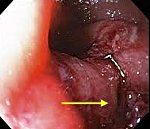

K22.3 Прободение пищевода